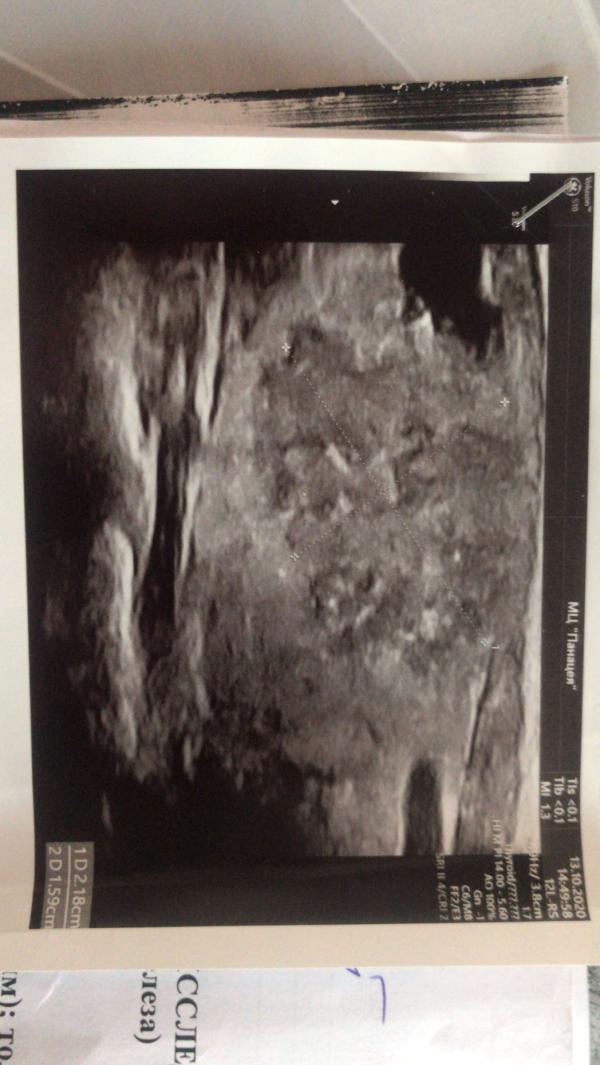

🆘 SOS!!! У меня Рак щитовидной железы подтвердили в НЦО. Объем 2 см - говорят нужно срочно оперировать. Дело в том что я беременна, идет 17 неделя. Может у кого есть знакомые, кто может проконсультировать? Рассматривается вариант операции заграницей( Турция, Россия: Москва, Новосибирск, С-Петербург, Корея) но в Корею сейчас невозможно говорят. Что делать? Сроки поджимают!!! Дайте совет. Каждый отзыв очень важен для меня🙏🏻 Пожалуйста

дело в том что. я беременна. и РЩЖ быстро прогрессирует. и лимфоузлы увеличены